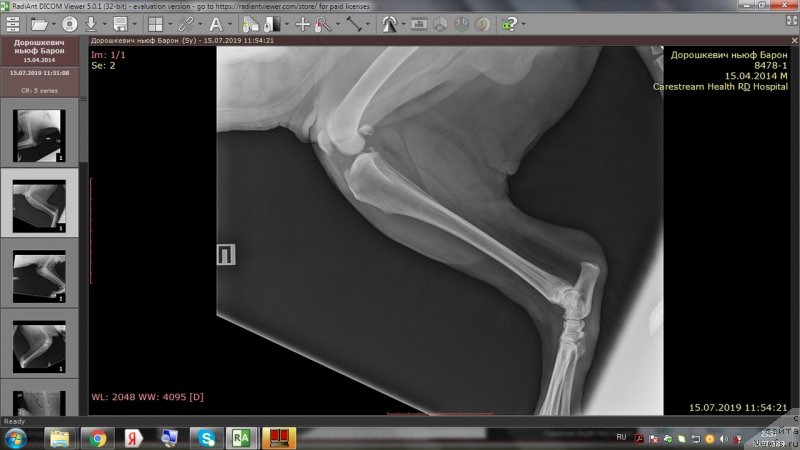

На приёме у врача.

Фотография № 243974

Фотография № 243976

Фотография № 243977

Фотография № 243978

Доброе утро,уважаемые форумчане!Вот и проползли черепашкой эти томительные 2 недели до повторного приема врача.И,вновь,к нашей радости,не подтвердились самые худшие опасения😊.Барошенька похудел на 3 кг.На снимках,как видно,в более-менее живом состоянии только правое колено.Локти не сгибаются из-за махровых наростов,с левым коленом ситуация хуже остальных лап,на прогулке,после лежания,первые несколько метров в колене слышно перестукивание суставов,но потом все проходит.Лечение идёт на пользу,колени стали лучше сгибаться,огромный отёк с левого колена спал,и писает теперь не приседая полностью до земли и не плюхаясь пузом от усталости в свою лужу.На прошлой неделе созванивались с доктором и немного подредактировали терапию-отменили тобрекс,т.к.не было результата и заменили на офтагель,флоксал,в связи с тем ,что у Бароши синдром сухого глаза и заворот века(рекомендовано в будущем провести операцию).Сегодня обновлю запасы этих лекарств.Антибиотик доксифин продлили до 8 недель,но купила пока на 2 недели,т.к.финансов не хватит на такой курс.Полное,качественное восстановление займет месяца 2.Сейчас то тут,то там выскочит экзема,соскоб с экзем показал наличие грибов-коки,эзофилы.Тут и стресс перенесенный и смена климата и т.д.